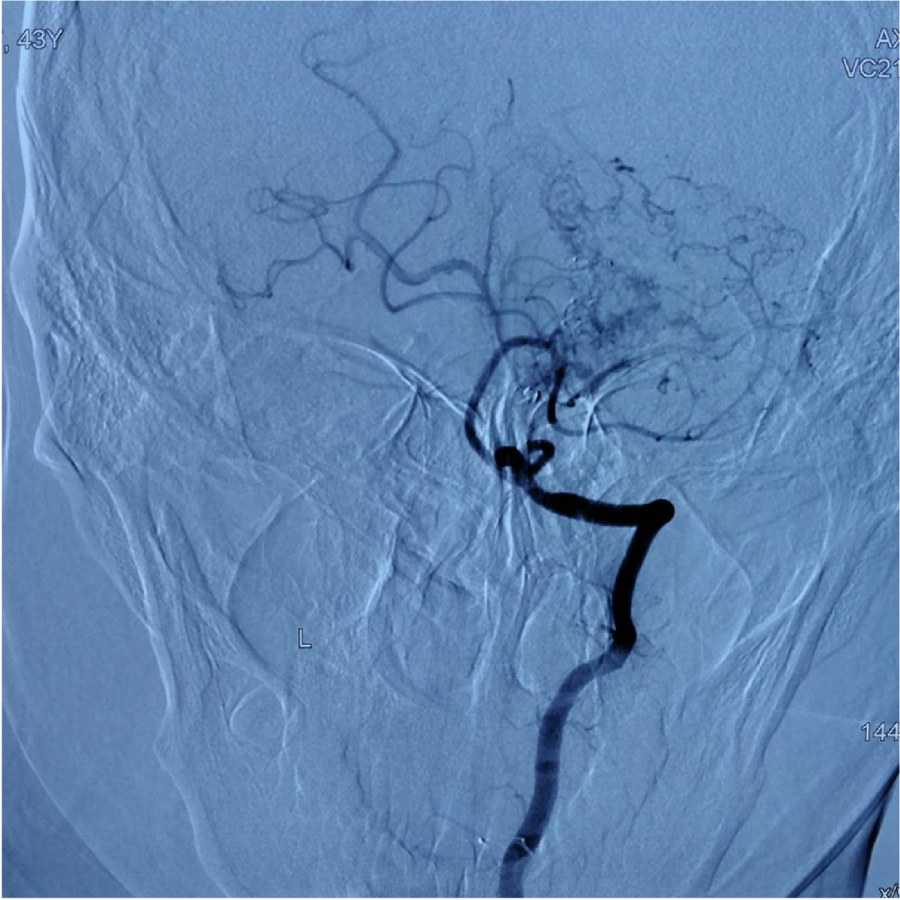

第⼀次DSA显⽰PICA供⾎

引流⾄⼄状窦

小脑后下动脉、小脑前下动脉参与供⾎

颈外动脉造影显⽰枕动脉参与供⾎

本次⼊院⾏DSA检查:PICA供⾎区有畸形⾎管团,引流到横窦